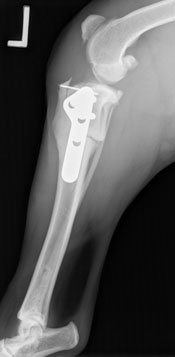

Fen was absolutely stable throughout surgery, and the rotation of the tibial plateau in both knees went well. After a night of hospitalization, Fen went home the next day, perky and moving well. He wanted to get back to his active lifestyle right away so his people had had to work diligently to hold him back. Recheck radiographs were taken 5 weeks after surgery, and Fen had already healed 60-70% of the cut. As you can see by the softening of the edges from the post-op radiograph to the 5 week recheck.

Fen was restricted for about 4 more weeks with increased leash walking to try and rebuild any muscling he may have lost. He continued to be strong and determined throughout his recovery. After being given the go ahead to resume normal activity, Fen was back to his Boykin ways, including his trademark “Boykin Bounce”. He bird hunts regularly and has the run of the 9 acres on the home farm.